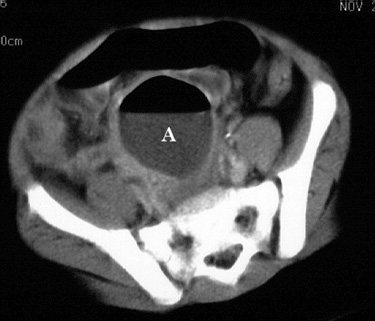

Figure 4. Contrast-enhanced CT image of the mid-pelvis shows a midline gas and fluid collection (A) consistent with an abscess. The appendix is not visible. |